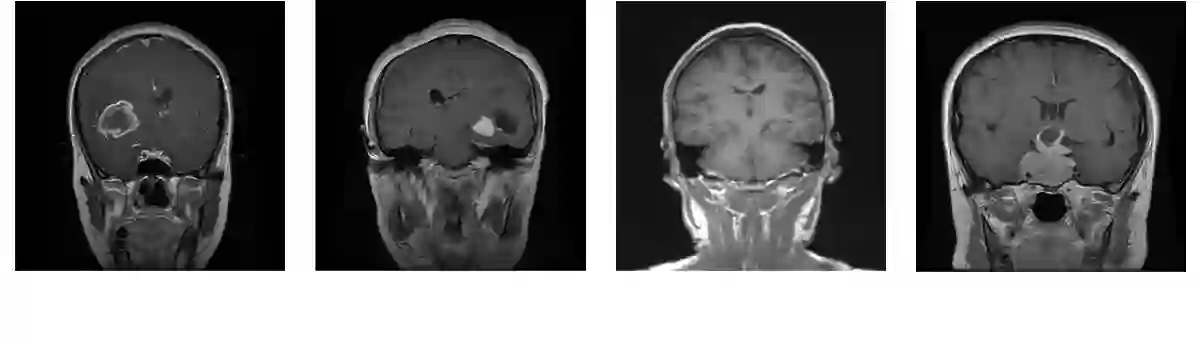

Brain tumors are among the deadliest diseases in the world. Magnetic Resonance Imaging (MRI) is one of the most effective ways to detect brain tumors. Accurate detection of brain tumors based on MRI scans is critical, as it can potentially save many lives and facilitate better decision-making at the early stages of the disease. Within our paper, four different types of MRI-based images have been collected from the database: glioma tumor, no tumor, pituitary tumor, and meningioma tumor. Our study focuses on making predictions for brain tumor classification. Five models, including four pre-trained models (MobileNet, EfficientNet-B0, ResNet-18, and VGG16) and one new model, MobileNet-BT, have been proposed for this study.

翻译:脑肿瘤是全球最致命的疾病之一。磁共振成像(MRI)是检测脑肿瘤最有效的方法之一。基于MRI扫描的脑肿瘤精准检测至关重要,因其可能挽救众多生命并在疾病早期阶段促进更优决策。本文从数据库中收集了四种不同类型的基于MRI的图像:胶质瘤、无肿瘤、垂体瘤和脑膜瘤。我们的研究聚焦于脑肿瘤分类预测。为此研究提出了五种模型,包括四个预训练模型(MobileNet、EfficientNet-B0、ResNet-18和VGG16)和一个新模型MobileNet-BT。